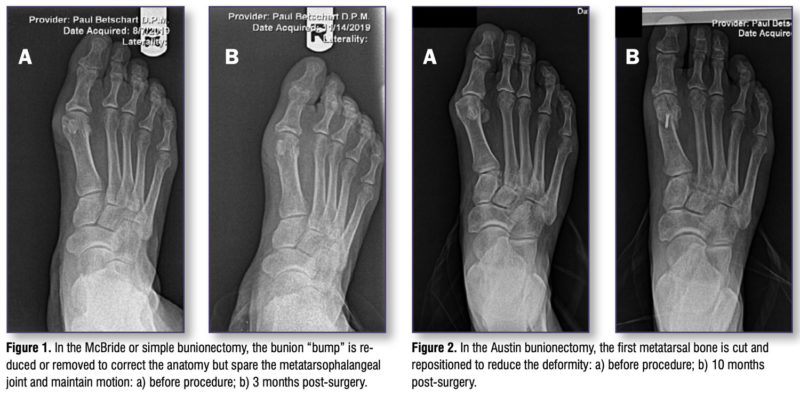

- Simple bunionectomy (-ectomy means surgical removal): In this procedure, the bunion “bump” is reduced or removed with various surgical instruments. This type of procedure has the shortest average recovery time and lends itself to minimally invasive techniques. It does not, however address the 3-plane nature of the deformity and the associated soft tissue imbalances that occur in the HAV deformity, thus making recurrence of the condition likely over time. Adding soft tissue release/re-balancing and/or adductor tendon transposition can help address the underlying issues and lessen the recurrence rates. The typical recovery time is 3-4 weeks in a surgical shoe, followed by 3-4 weeks in sneakers or other roomy footwear. Impact activities can usually resume after 4 weeks as tolerated. My preference is to reserve this type of procedure for mild deformities or for patients whose bone quality would make bone procedures ill advised. See Figure 1.

- First metatarsal osteotomy (osteotomy means surgical cutting of bone or removal of a piece of bone): In this procedure, the first metatarsal bone is cut and repositioned to reduce the deformity. There are numerous techniques described for this type of procedure. The most commonly performed is the distal chevron osteotomy, also known as the Austin bunionectomy. A small surgical saw is used to cut through the metatarsal at the end closest to the toe. The end of the bone is then shifted toward the second metatarsal and secured to the other segment with a small screw or pin for stability during bone healing. The geometry of the bone cut makes it very stable, allowing for immediate post-operative protected weight bearing. On its own, it is also not a 3-plane correction. As with the simple bunionectomy, adding soft tissue release/re-balancing and tendon transposition can help improve the correction and reduce recurrence rates. This is a versatile procedure that can address the mild to moderate bunion effectively. It has the advantage of being able to be performed in an office surgical suite setting, under local anesthesia, potentially saving out-of-pocket costs for patients with high deductible health plans. The recovery period is typically 4-6 weeks in a surgical shoe followed by 4-6 weeks in sneakers or other loose-fitting shoes. Impact activities can usually be resumed at 8-10 weeks. See Figure 2.